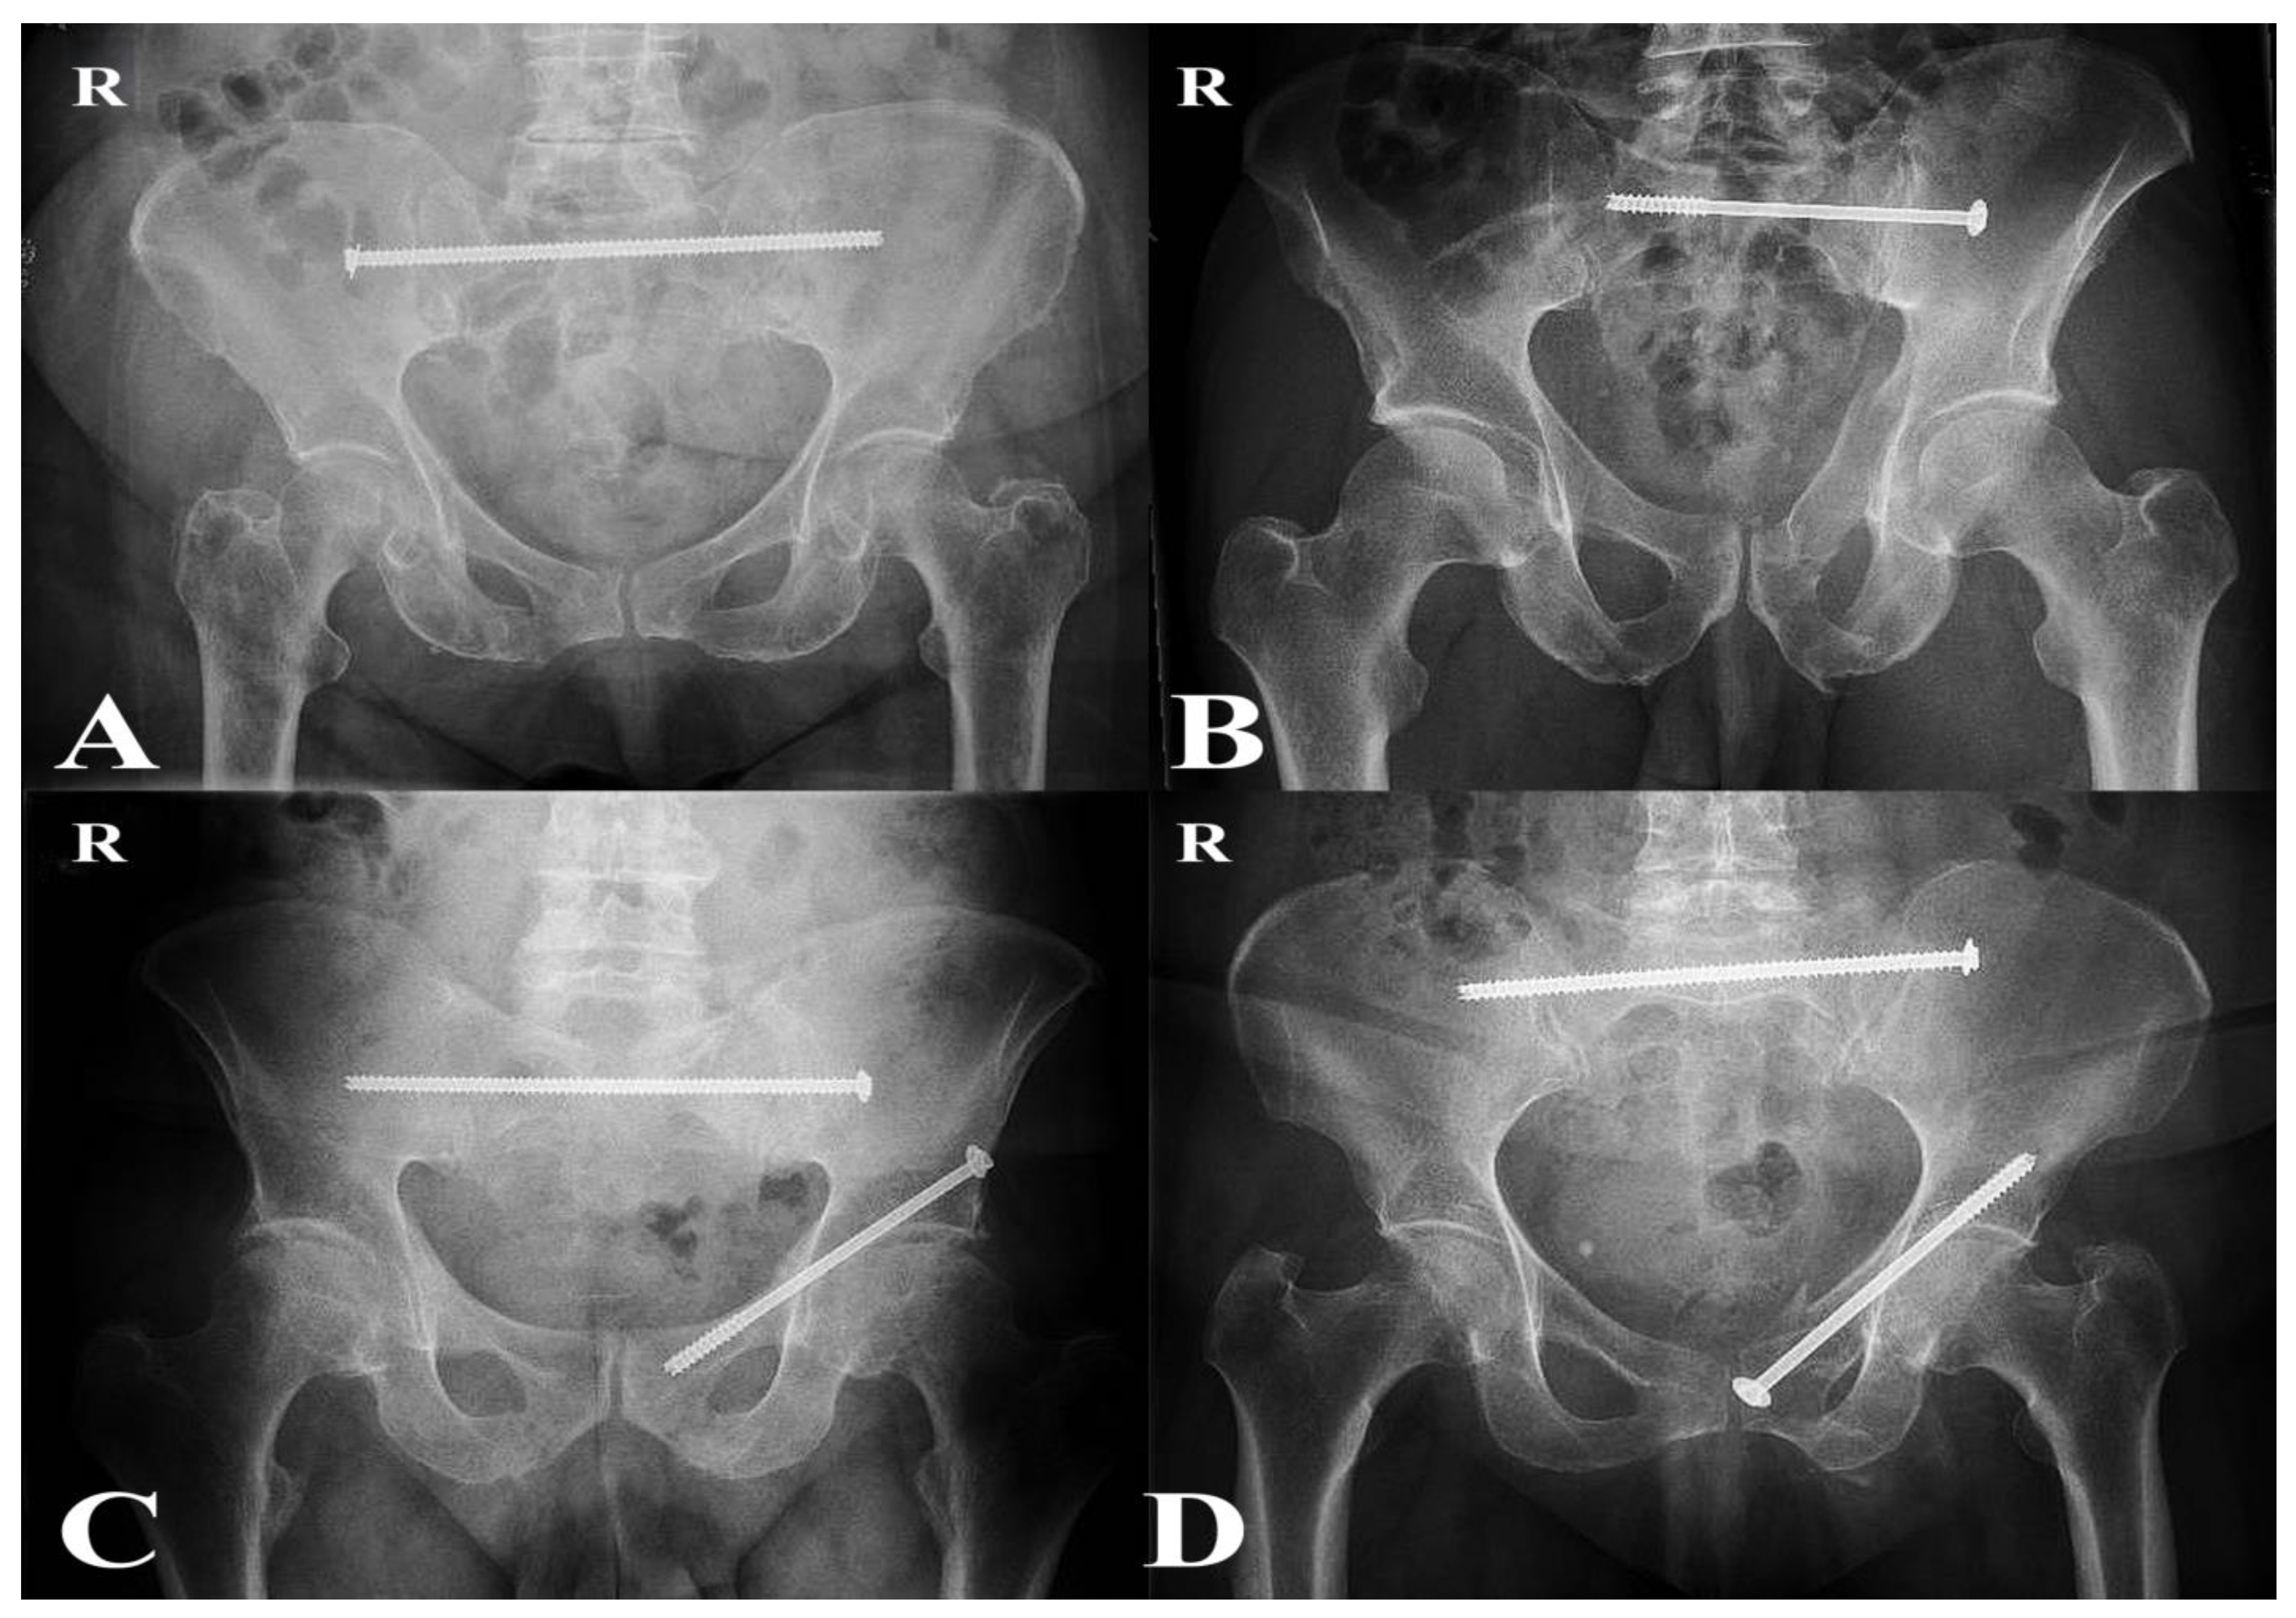

2.5. Surgical Procedures

Operations were performed by approximately six senior orthopedic trauma surgeons with subspecialty expertise in pelvic and acetabular surgery. All patients underwent percutaneous fixation under fluoroscopic guidance in the supine position. Trans-iliac trans-sacral (TITS) screws were the preferred technique for posterior fixation. Patients with sacral dysmorphism and incomplete sacral fractures were treated with sacroiliac screws (SIS), which were considered sufficient to provide adequate posterior stability [22]. For anterior fixation, patients received either antegrade or retrograde pubic ramus screws, depending on the individual fracture morphology (Figure 2) [23].

Figure 2. Postoperative radiographs extracted from the hospital’s radiology system (Philips IntelliSpace PACS) illustrating fixation techniques used in both groups. (A) Transiliac–transsacral (TITS) screw fixation (P-Fix group); (B) Sacroiliac screw (SIS) fixation (P-Fix group); (C) Combined TITS and retrograde anterior ramus screw fixation (C-Fix group); (D) Combined TITS and antegrade anterior ramus screw fixation (C-Fix group). The letter “R” denotes the right side of the pelvis.